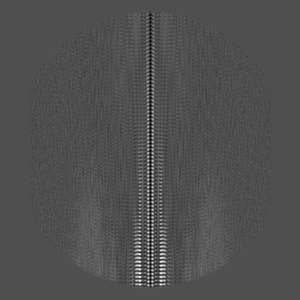

Cryo-EM reconstruction of TypeII tau filaments extracted from the brains of individuals with Corticobasal degeneration

Helical reconstruction3.0 Å

Sample: Tau filaments extracted from the Frontal cortex of a patient with corticobasal degeneration.